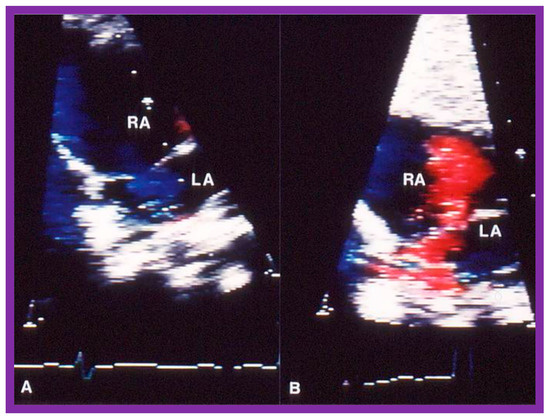

4.2. Aortic Stenosis

Aortic Stenosis in the Fetus